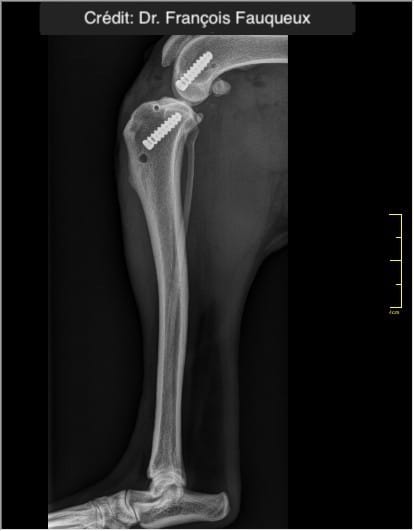

Radiologické snímky